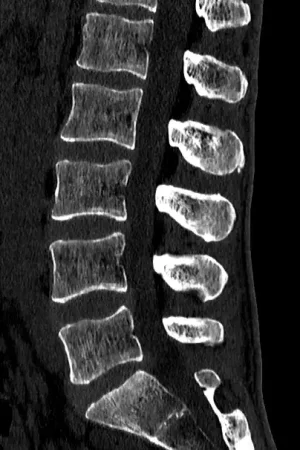

TK (CT) - tomografia komputerowa

Tomografia komputerowa to bardzo duża ilość zdjęć RTG, połączona ze sobą za pomocą odpowiednich algorytmów. Stosowana rzadziej, głównie gdy MRI nie może być wykonany (np. z powodu wszczepionego rozrusznika serca).

Na tomografii komputerowej można ocenić przede wszystkim struktury kostne. Jest więc przydatne w ocenie złamań kręgów. Ponadto jest to najdokładniejsze badanie w ocenie kręgoszczelin.

Na TK można też ocenić:

- (częściowo) stan krążków międzykręgowych,

- uwapnienia okolicznych tkanek, w tym blaszki miażdżycowe np. w obrębie aorty brzusznej.